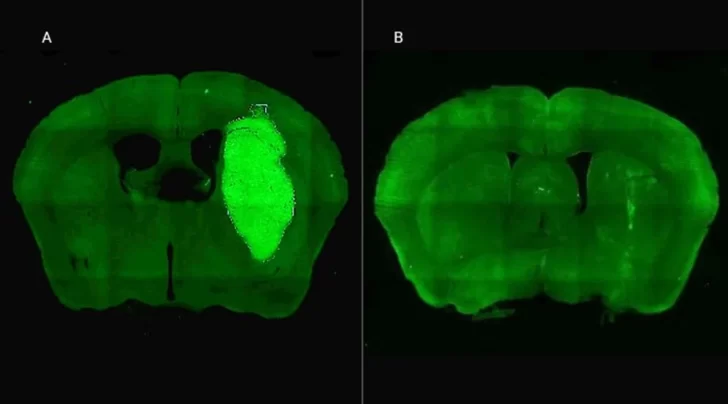

Candolfi y colegas utilizaron una terapia génica experimental basada en una molécula muy pequeña o péptido llamado P60, desarrollado por Juan José Lasarte en la Universidad de Navarra, en España, que atraviesa la membrana celular e inhibe la proteína Foxp3. “Cuando en experimentos de laboratorio bloqueamos Foxp3 utilizando P60, la respuesta de las células de glioblastoma a la radioterapia y a una variedad de drogas quimioterapéuticas mejoró notablemente”, destacó la investigadora del CONICET.

Además, P60 tuvo efectos antitumorales directos, reduciendo la viabilidad y la migración de las células de glioblastoma e inhibiendo la proliferación de células endoteliales que son clave para la progresión del tumor. Para evaluar estos efectos, los autores del estudio utilizaron una variedad de modelos celulares murinos (de roedor) y humanos. “En particular, los cultivos derivados de biopsias de pacientes con glioblastoma desarrollados por nuestro colaborador Guillermo Videla Richardson, del Instituto FLENI, son muy útiles para representar la heterogeneidad de estos tumores”, indicó Candolfi.